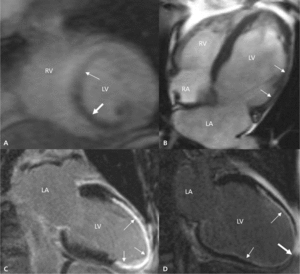

Najczęściej stosowane sposoby oceny niedokrwienia oraz żywotności mięśnia sercowego za pomocą CMR przedstawiono w tabeli 1.Przykłady niektórych badań zaprezentowano na rycinie 1.

Najczęściej stosowana technika analizy żywotności polega na ocenie tzw. późnego wzmocnienia pokontrastowego (delayed enhancement, DE). W obrębie cechującej się dużą objętością przestrzeni pozakomórkowej blizny pozawałowej dochodzi do zalegania podanego do żyły obwodowej gadolinowego środka kontrastowego (substancji pozakomórkowej), co powoduje charakterystyczne wzmocnienie tego obszaru mięśnia (jaśniejszy kolor w skali odcieni szarości) po ok. 10-15 minutach. W praktyce o zachowanej żywotności mówi się, gdy w danym segmencie grubość obszaru DE nie przekracza 50% grubości mięśnia [8]. Oceniono, że przy tak zdefiniowanym punkcie odcięcia NPV testu (tzn. brak poprawy czynności skurczowej po rewaskularyzacji przy DE ≥50%) wynosi ok. 80% [5,9]. Nieco niższa jest za to wartość PPV (tzn. poprawa czynności skurczowej po rewaskularyzacji przy DE <50%), która wynosi ok. 70% [5,9]. Badanie z samym środkiem kontrastowym (podobnie do EDWT) nie pozwala ocenić, czy dysfunkcyjny obszar mięśnia z DE obejmującym <50% grubości ściany posiada rezerwę skurczową.

Przy granicznych wartościach DE (25-75%) zaleca się połączenie obu metod i wykonanie oceny żywotności za pomocą DE oraz próby z dobutaminą [1]. W praktyce takich sytuacji jest jednak niewiele, ponieważ w celu kwalifikacji do rewaskularyzacji mięśnia ocenę pojedynczych segmentów należy odnieść do poszczególnych ścian lewej komory (6-7 segmentów), a grubość warstwy DE rzadko pozostaje graniczna we wszystkich ocenianych segmentach (ryc. 1D).